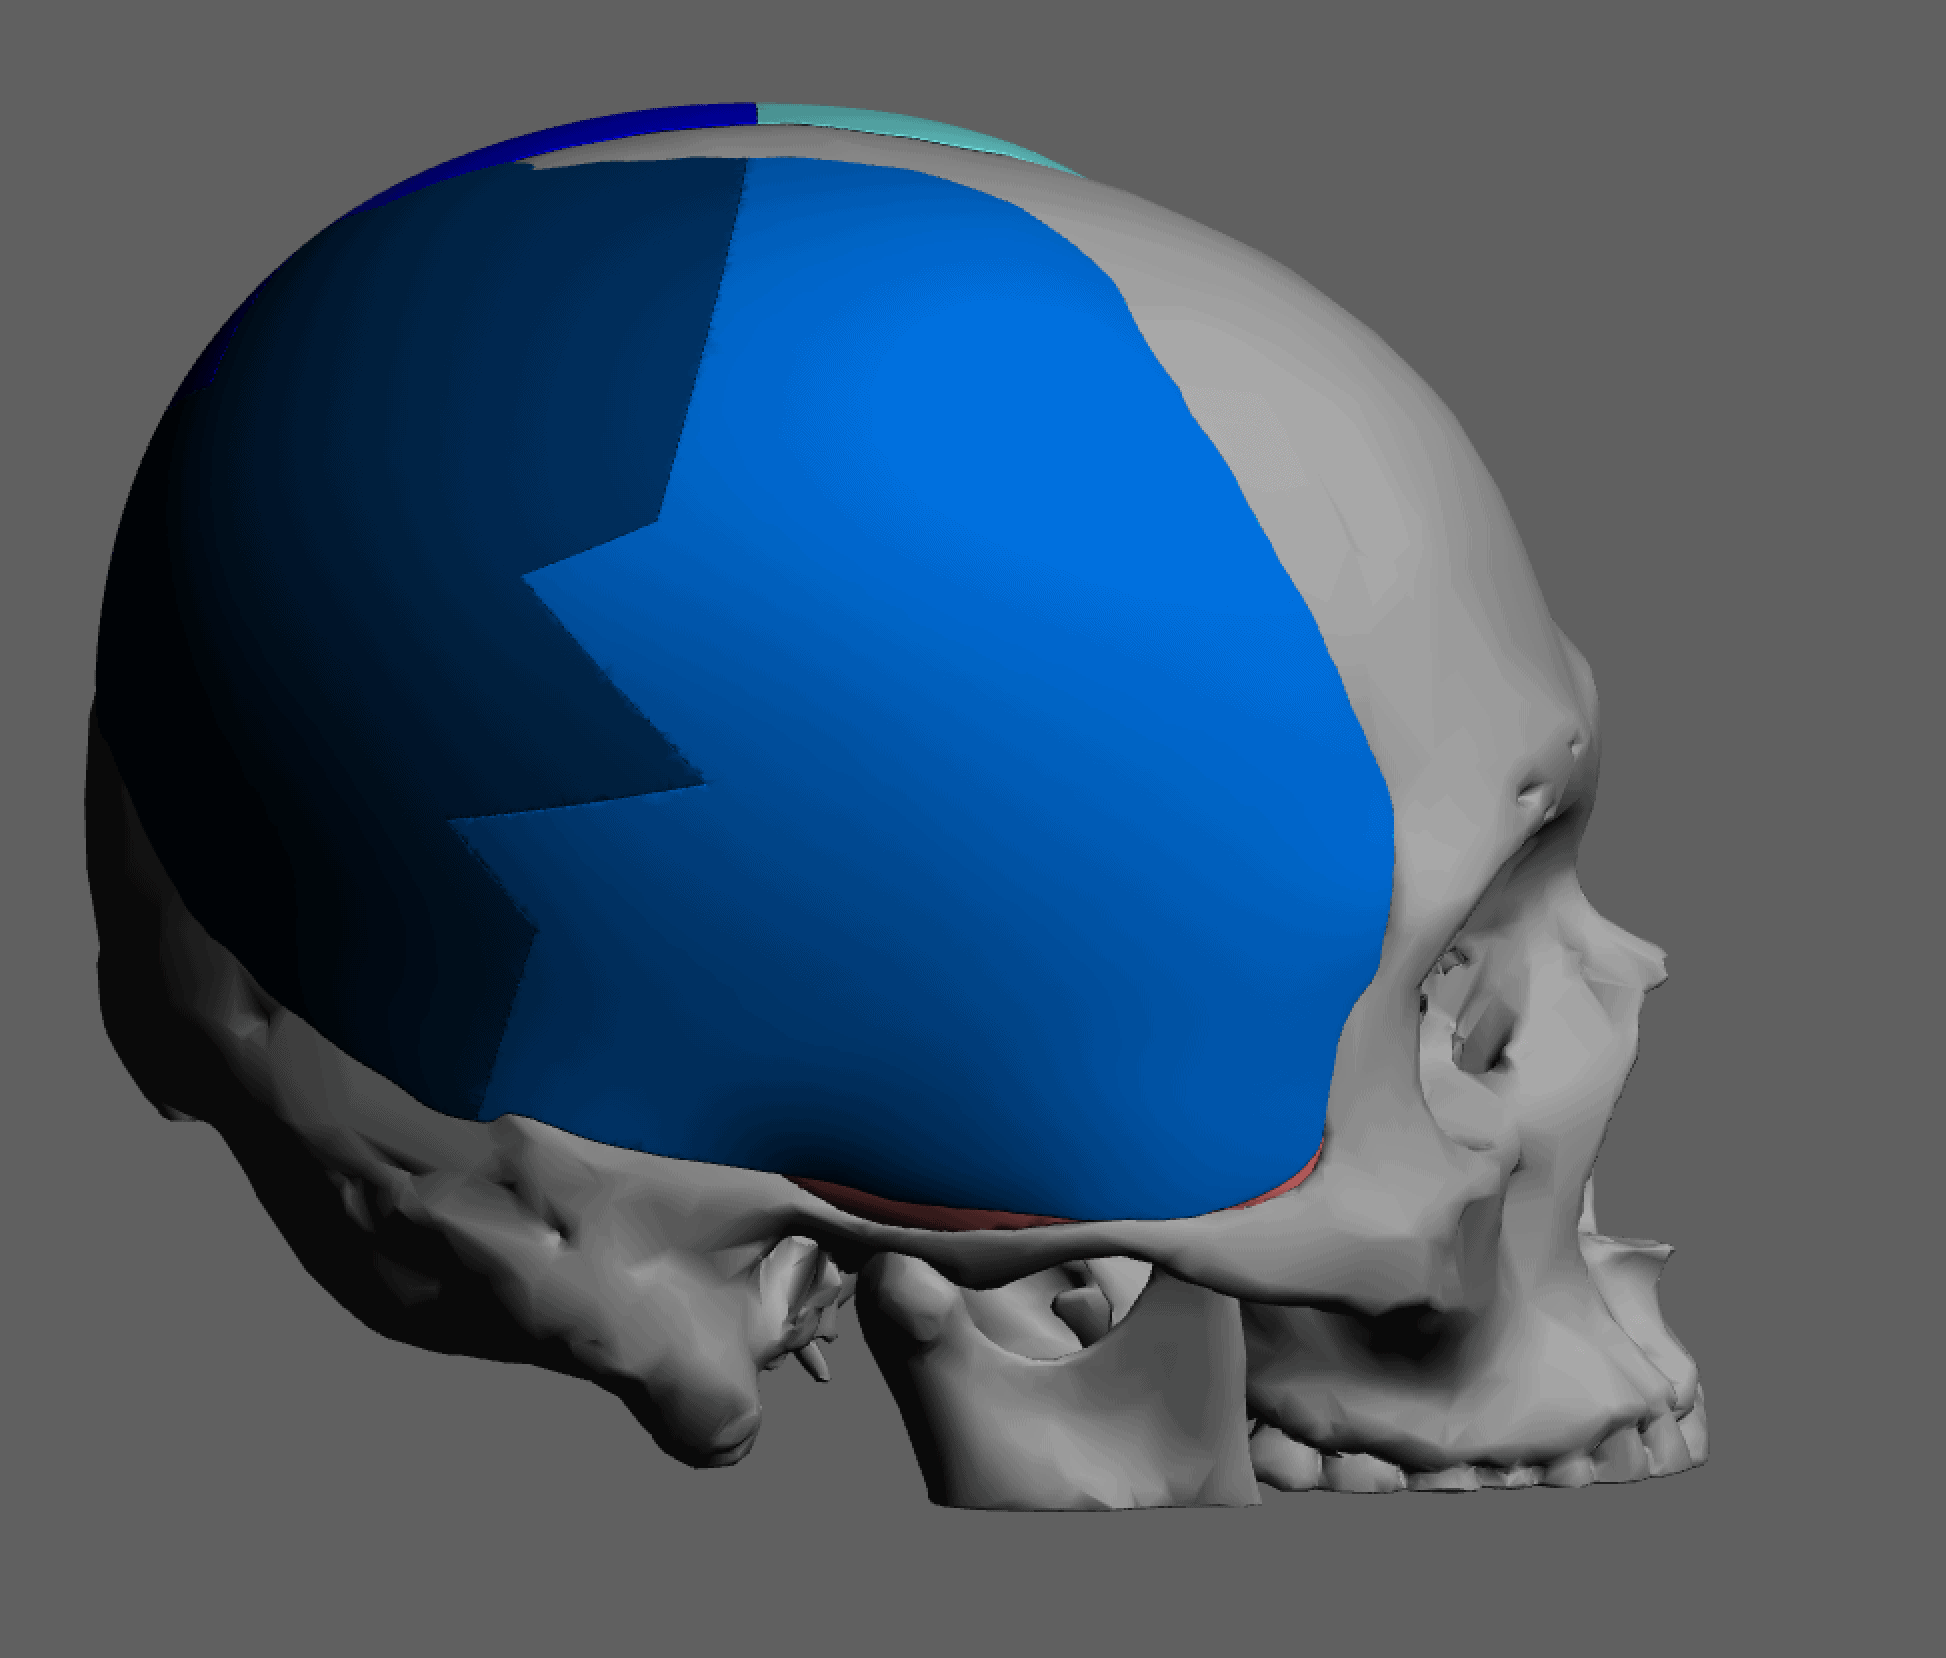

Desire for major head reshaping with a taler and wider head shape.

Placement of large two piece custom skull implant through a sagittal scalp incision.

Desire for major head reshaping with a taler and wider head shape.

Placement of large two piece custom skull implant through a sagittal scalp incision.